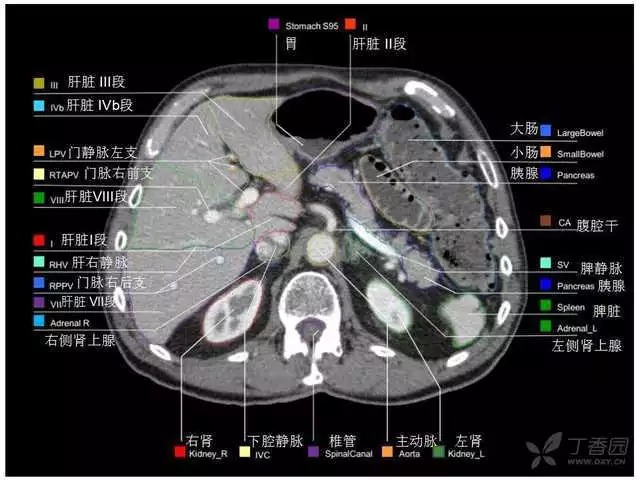

腹部肝脏高清CT断层的图谱

全腹部高清CT图谱,淋巴结彩色图谱,血管解剖图谱大汇总!

肝段,肝内管道的分布规律